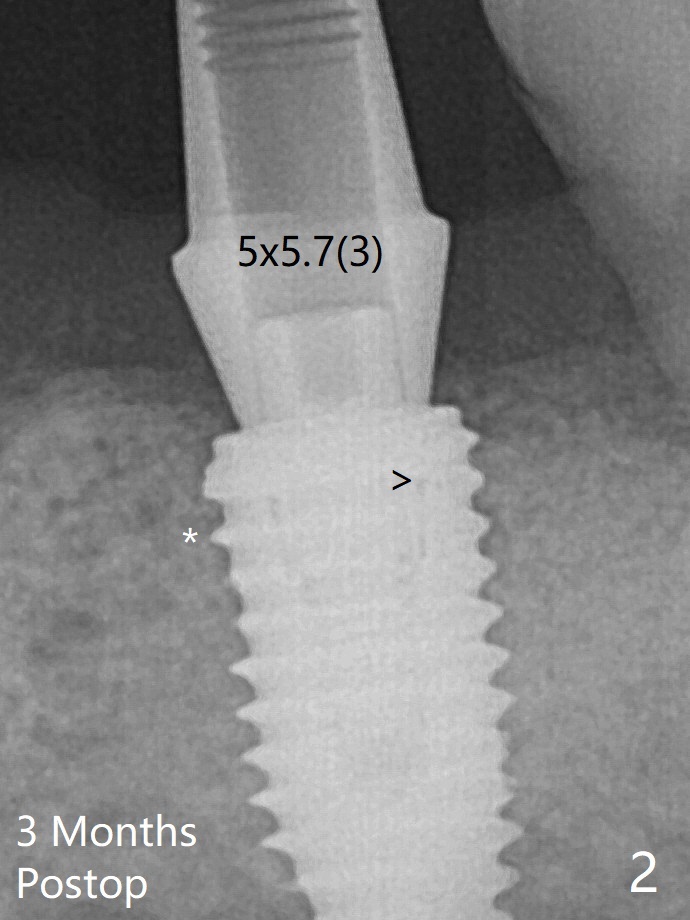

更换4.5x7(4)毫米UF基台就位仿佛改善(图三),降低基台高度后取模。